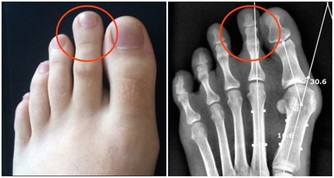

肺部有毒的表現症狀

肺毒的原因:肺毒也叫氣毒,主要和空氣品質有關,

另外肺毒跟吃有相當大的關係,重慶人愛吃醃制食品,

比如香腸、臘肉,腸道容易堆積毒素,從而對肺的傷害很大,即中醫所說的肺與大腸相表裡。

所以,假如排泄不暢,便秘,會導致大腸內毒素增加,繼而傷肺。

肺毒的表現:呼吸不暢、胸悶、咳痰。